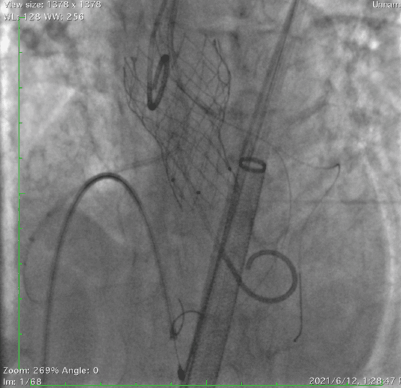

跨瓣成功,采用双侧冠脉双导丝保护 。

在超硬导丝交换后,给与左室充分的时间适应急性AR带来的低血压,上调正性肌力药使血压稳定后,使用20mm球囊扩张,有明显腰征,无瓣周漏,左冠距离远,右冠血流中断。证实术前判断,球扩后患者低血压缓慢恢复,加强正性肌力药支持。